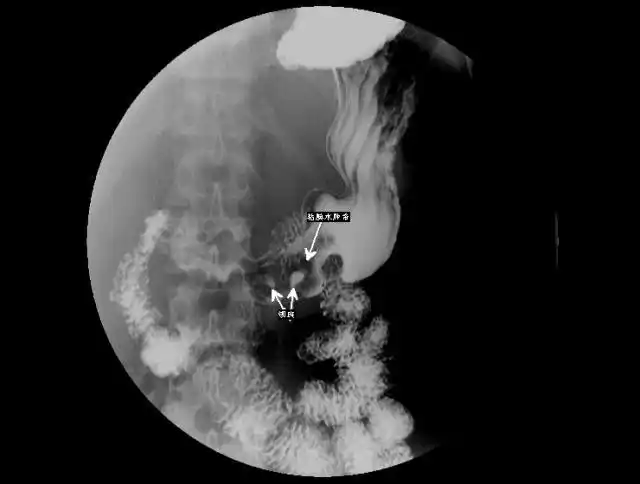

2胃溃疡2.jpg